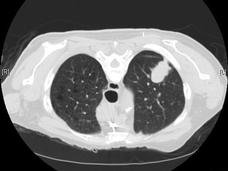

Lung Cancer Screening Pilot Reveals Challenges, Growing Pains

A demonstration project by the Veterans Health Administration is highlighting some of the complexities and challenges associated with the expansion of lung cancer screening in the United States.